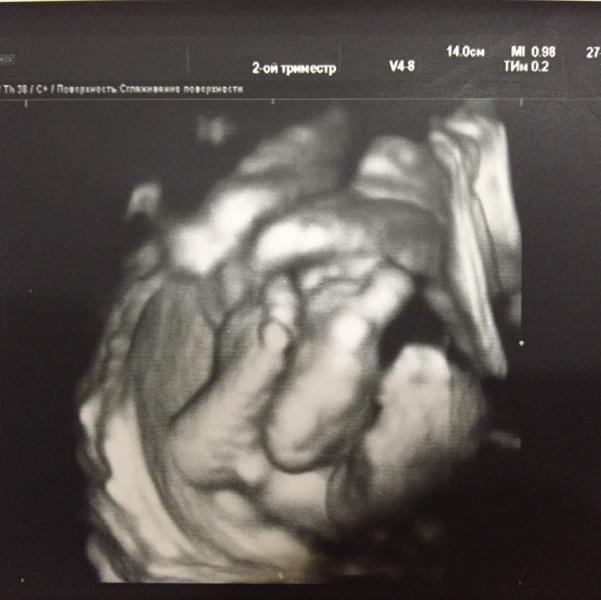

Любимая моя, радость моя😍 столько впечатлений от 3d узи, их все просто не описать😊 самое главное, что у нас всё очень даже хорошо😊 по её положению и позе в животике это сразу видно))) лежит себе поперек, нога на ногу, отдыхает😂😜😘 не жалейте денег и обязательно сходите, впечатления на всю жизнь☺️❤️

@alibayevaa, мы вчера были у неё, самые последние по записи😊 она нас ооочень тщательно из-за этого рассматривала☺️ диск она не стала делать, потому что доча личика не показывала всё время, прятала ручонками😂😀 но в конце сдалась и показала))) только снимки сделали😍

@sofidave, и так тоже хорошо, на 25 неделе впринципе также почти, по частям, ножку, голову, пузико😂))) наша еще показываться не хотела, но мы её поймали, они подглядывала и улыбнулась нам😍😜😂

Ой какой милый снимок😍 не могла не оставить коммент, какие ножки малюсенькие миленькие😍 а где вы делали?